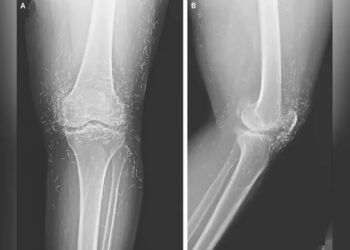

Dokter Temukan Ratusan Benang Emas Tertanam di Lutut Pasien di Korea Selatan, Terungkap Lewat Rontgen

IKNPOS.ID - Dokter di Korea Selatan terkejut menemukan ratusan benang emas tertanam di lutut seorang pasien wanita berusia 65 tahun. Penemuan tak biasa...